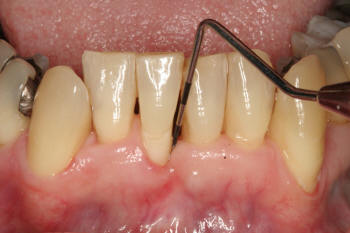

Grado 0 |

Grado 1 |

Los

dientes y los sitios seleccionados para aplicar

el índice de hemorragia simplificado son los mismos que los tomados en el

índice gingival.